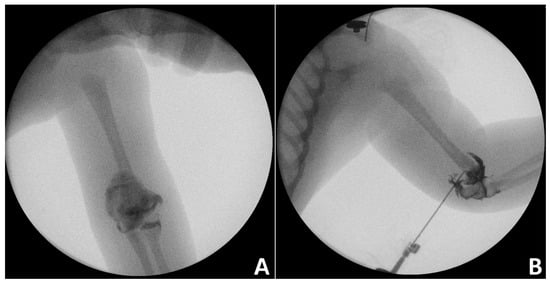

In infants and toddlers, elbow arthrogram is usually performed during CRPP of DHPS to improve anatomic reduction in the distal humerus (Figure 3) [28].

Figure 3. Intraoperative elbow arthrography images of an infant with distal humerus physeal separation (A) Anteroposterior view, (B) lateral view.

However, Chou et al. [29] suggested that, instead of intraoperative arthrogram, fracture reduction could be safely evaluated by checking if the ulnar axis was within the boundaries of the medial and lateral humeral lines. The authors reported that the method was associated with decreased incidence of cubital varus deformity.